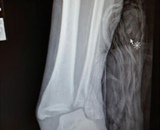

At the 2015 Turkey Meet at Skydive City Zephyrhills in Florida, my canopy collapsed at 20 feet as I was coming in on final. I broke the fibula at my left ankle and dislocated and fractured my tibia. The abrupt plunge also caused intense fear and anxiety about skydiving. Mechanical turbulence caused the accident: I landed close to the hangar and the wind rolling over it and into the landing area collapsed my parachute.

On the second jump, I felt a sudden bump and a significant drop at around 900 feet. All I wanted to do then was land and check the wind conditions. As I came around to final, I noticed I was not traveling forward much. I was getting ready to pull my toggles down to flare when I dropped straight down and landed flat on my feet. My left foot landed on a patch of overgrown grass and I rolled hard on my ankle. The snap, crackle and pop told me I had broken bones. The experience was surreal.